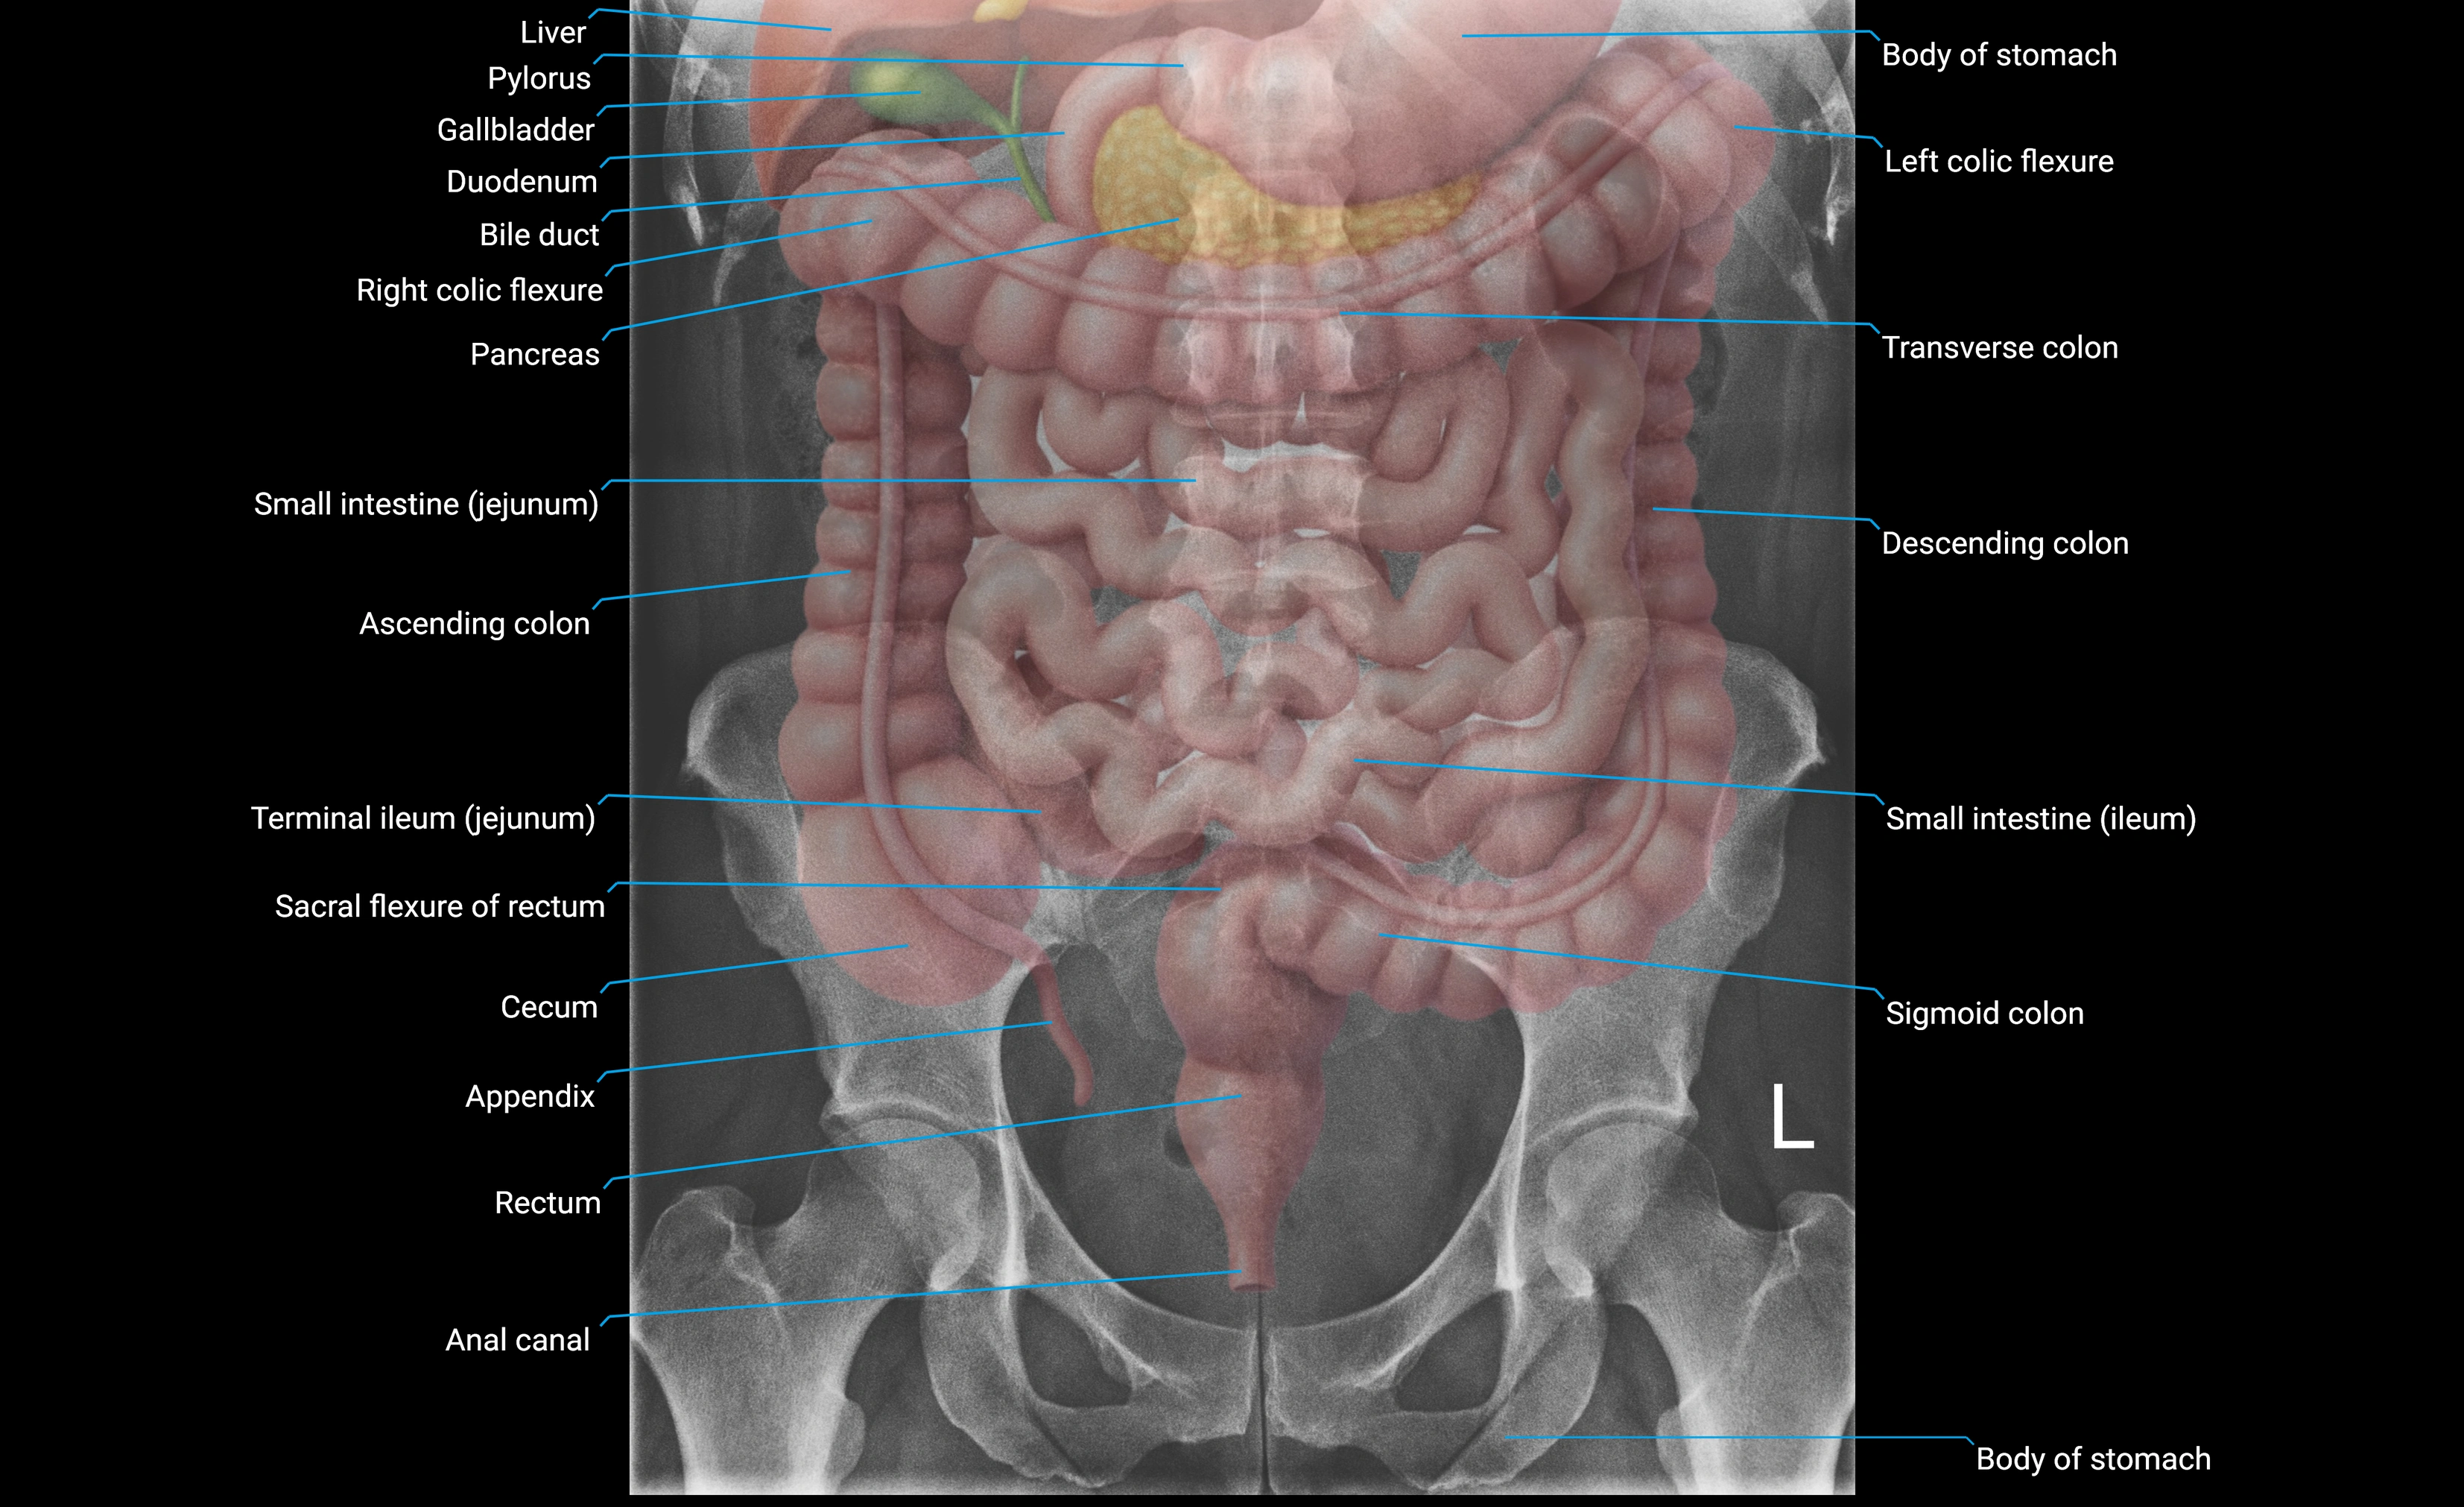

CT Appearance

Non-Contrast CT:

• Accessory process appears as a small bony outgrowth at the posterior base of the transverse process

• Clearly visualized due to high resolution of cortical bone

• Useful for detecting fractures, bony hypertrophy, or congenital variations